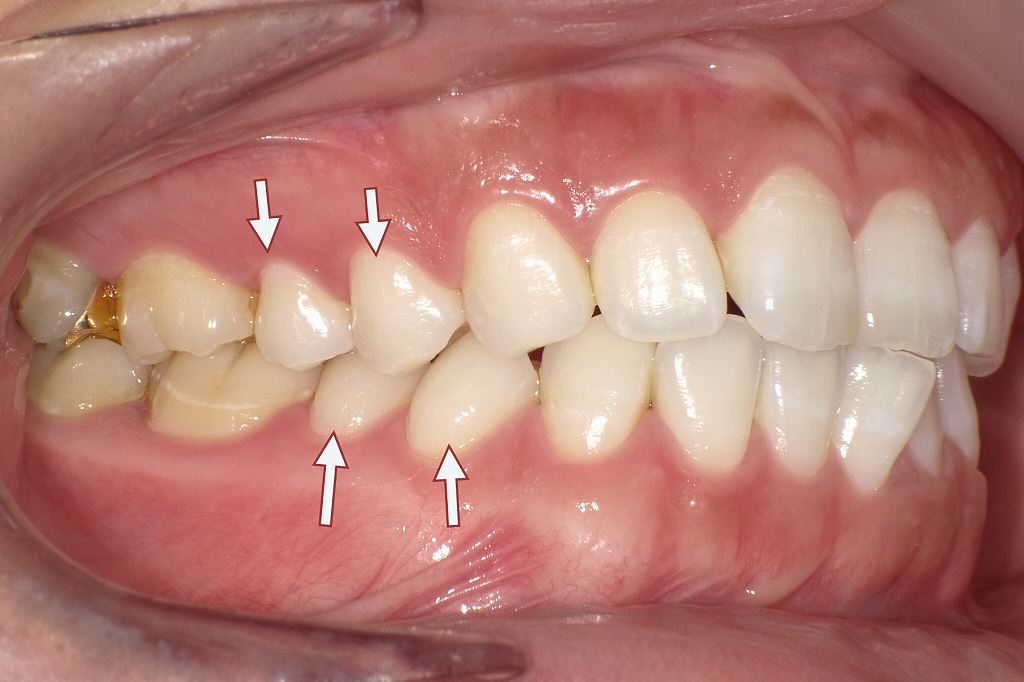

下記の口腔内写真は歯の萌出スペースが足りない、あるいは周囲の歯との位置関係が乱れている場合、小臼歯が本来の歯列から外れて生えてしまうことがあります。これが「頬側転移(きょうそくてんい)」や「舌側転移(ぜっそくてんい)」と呼ばれる現象です。